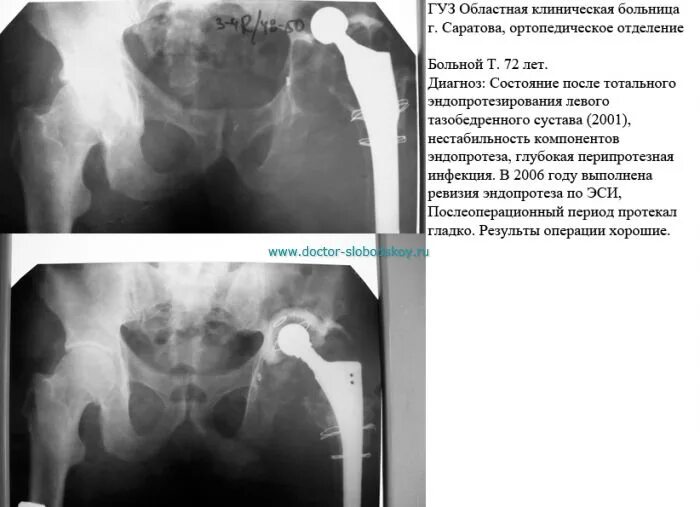

Вывих после эндопротезирования тазобедренного